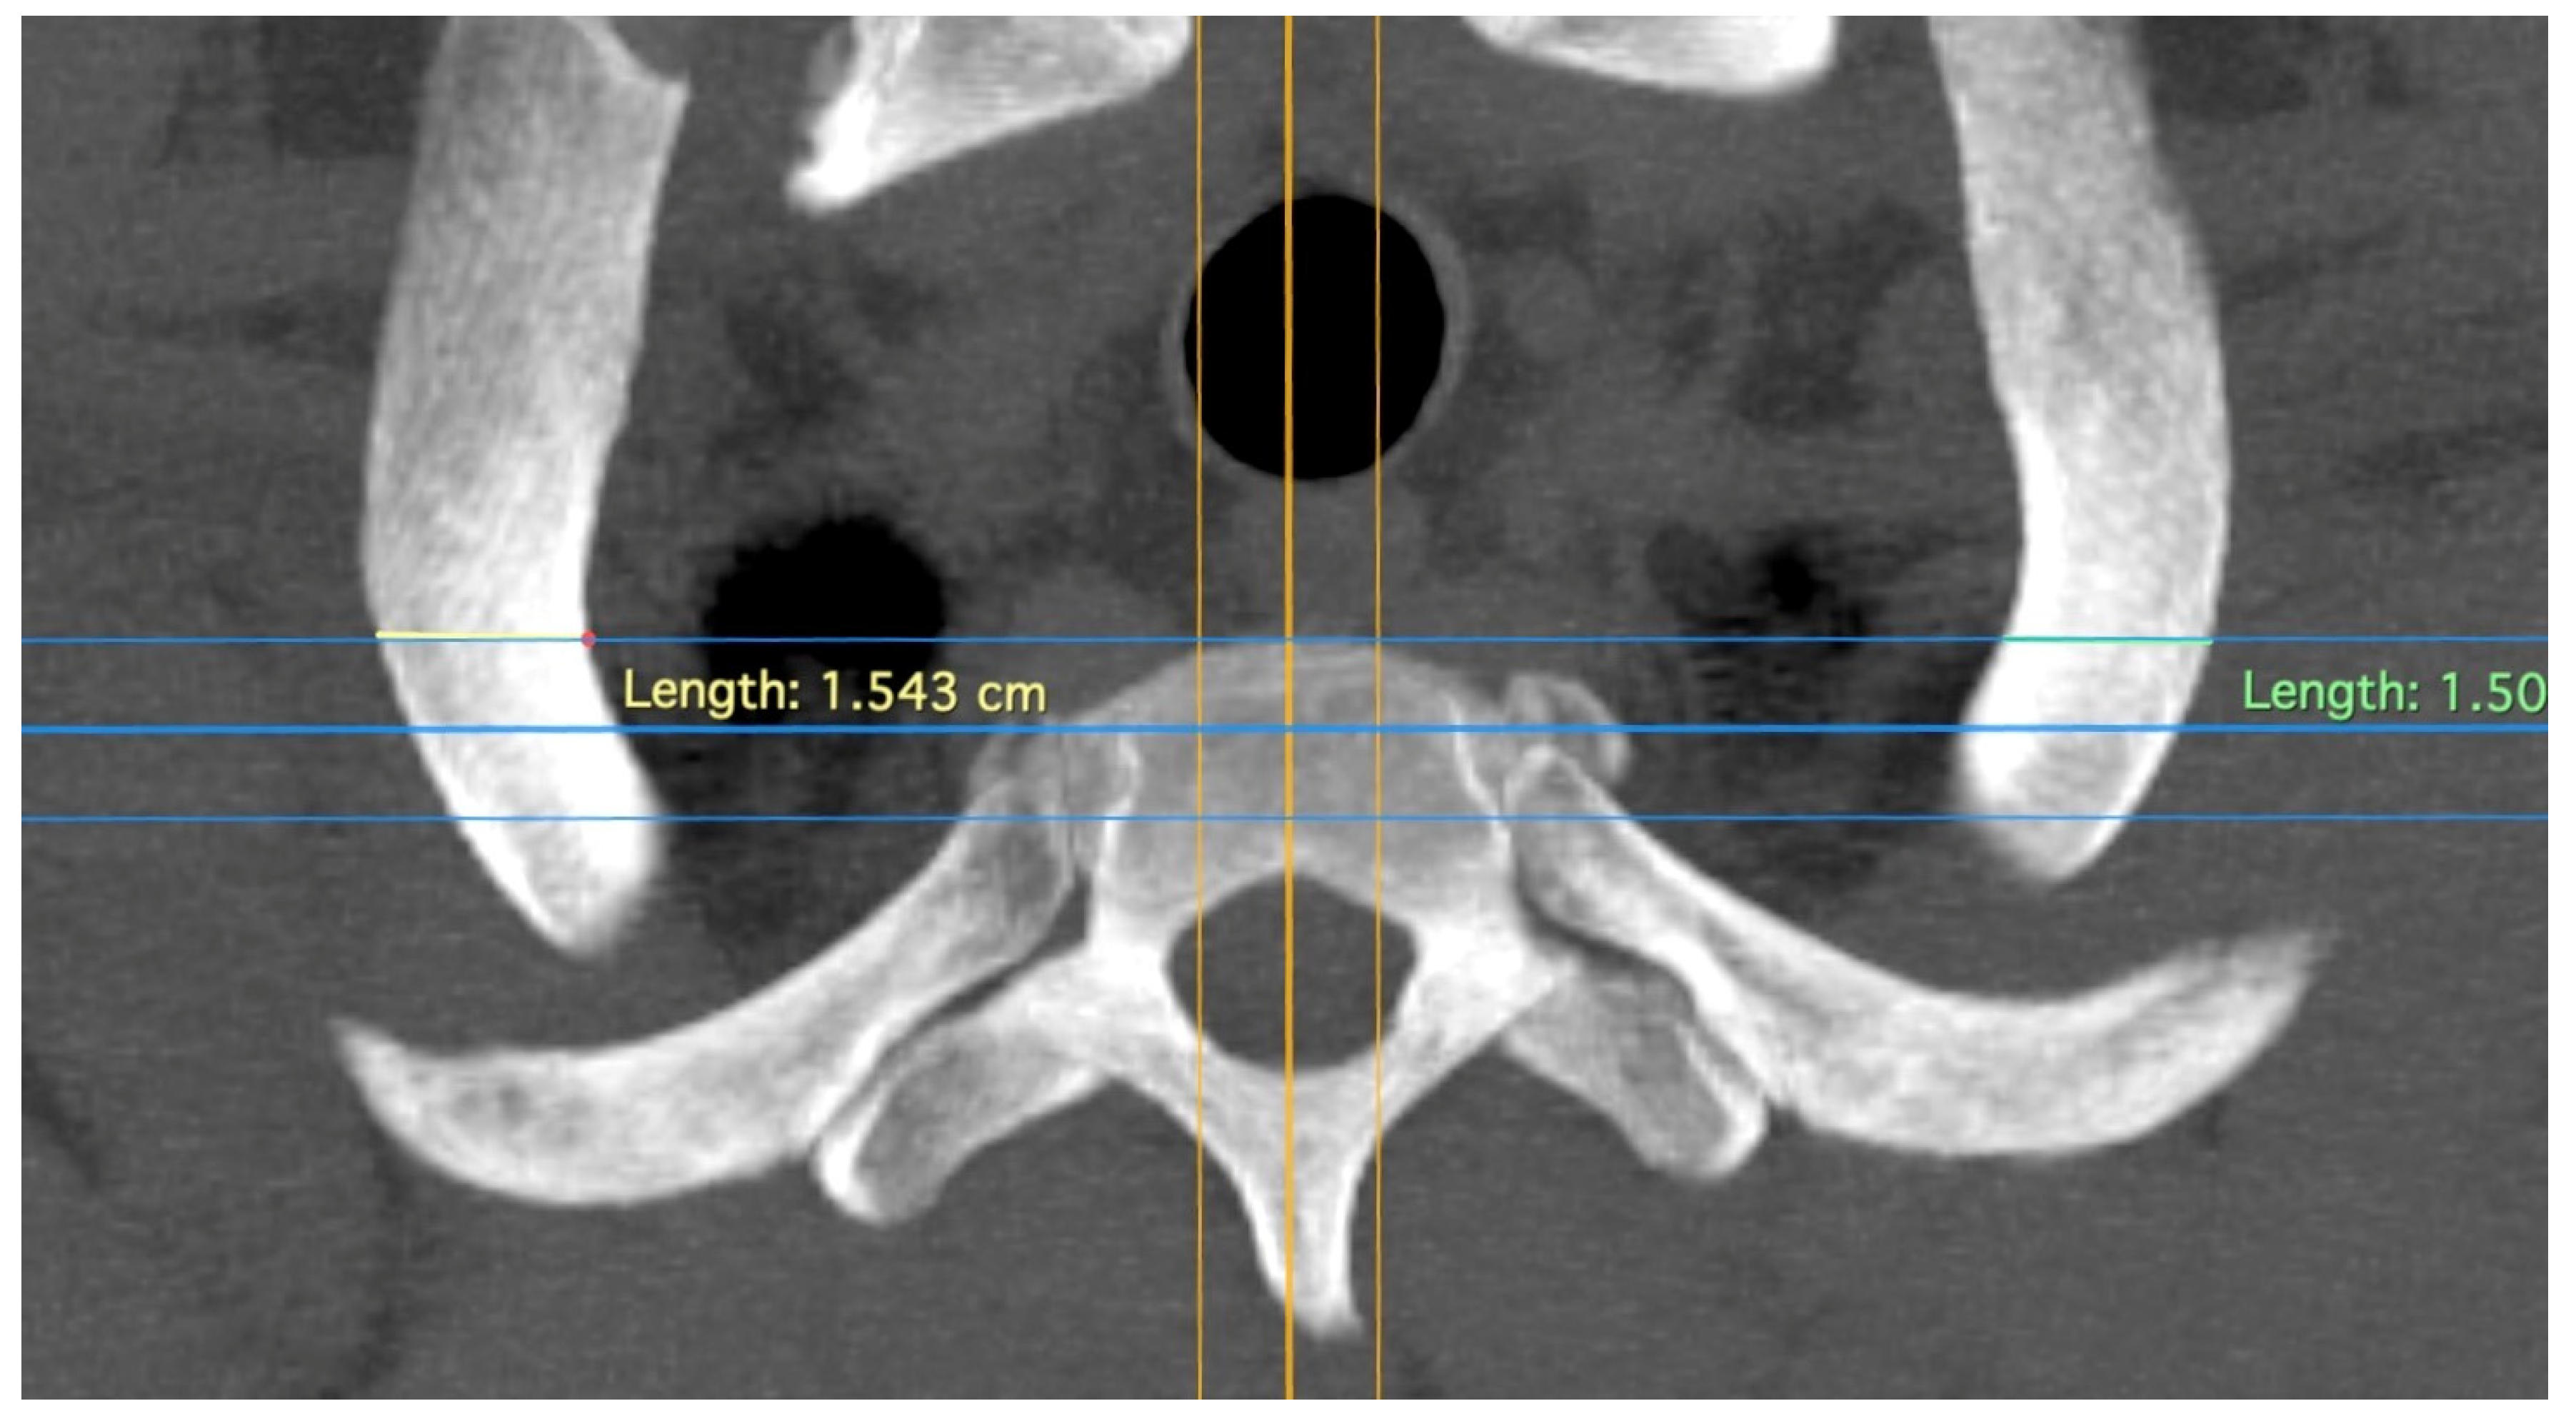

Figure 3.

Measurement of rib width; thick yellow line indicating the sagittal plane; upper blue line marking the anterior edge of the first thoracic vertebra, the plane in which the Th1 root passes over the first rib with direct contact to the rib. Differently colored lines for better differentiation.